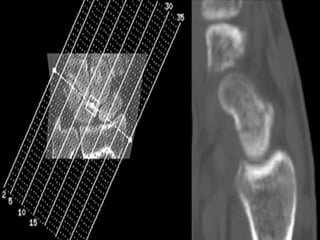

CT Scans

 CT permits accurate anatomic assessment of the fracture.

 Bone contusions are not evaluated with CT, but true fractures

can be excluded

CT Scans  CTpermits accurate anatomic assessment of the fracture.  Bone contusions are not evaluated with CT, but true fractures can be excluded